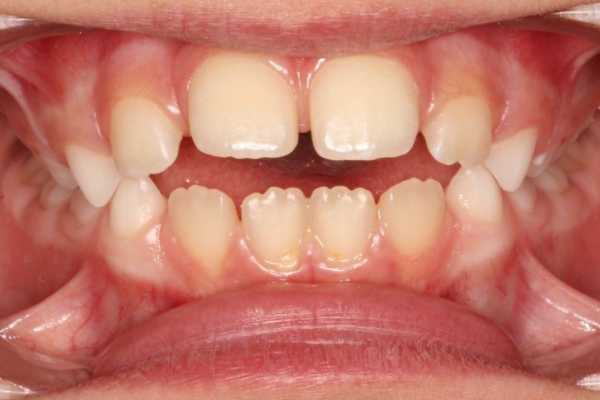

Observar y Actuar en el momento preciso permite intervenir en las etapas tempranas del crecimiento, lo que puede simplificar o incluso evitar tratamientos ortodóncicos complejos en el futuro.

La Supervisión del Crecimiento de nuestros hijos es fundamental para garantizar un desarrollo bucal adecuado.

Con una atención cuidadosa en las fases clave del desarrollo, podemos asegurar una Salud bucal óptima y Resultados duraderos para nuestros hijos.